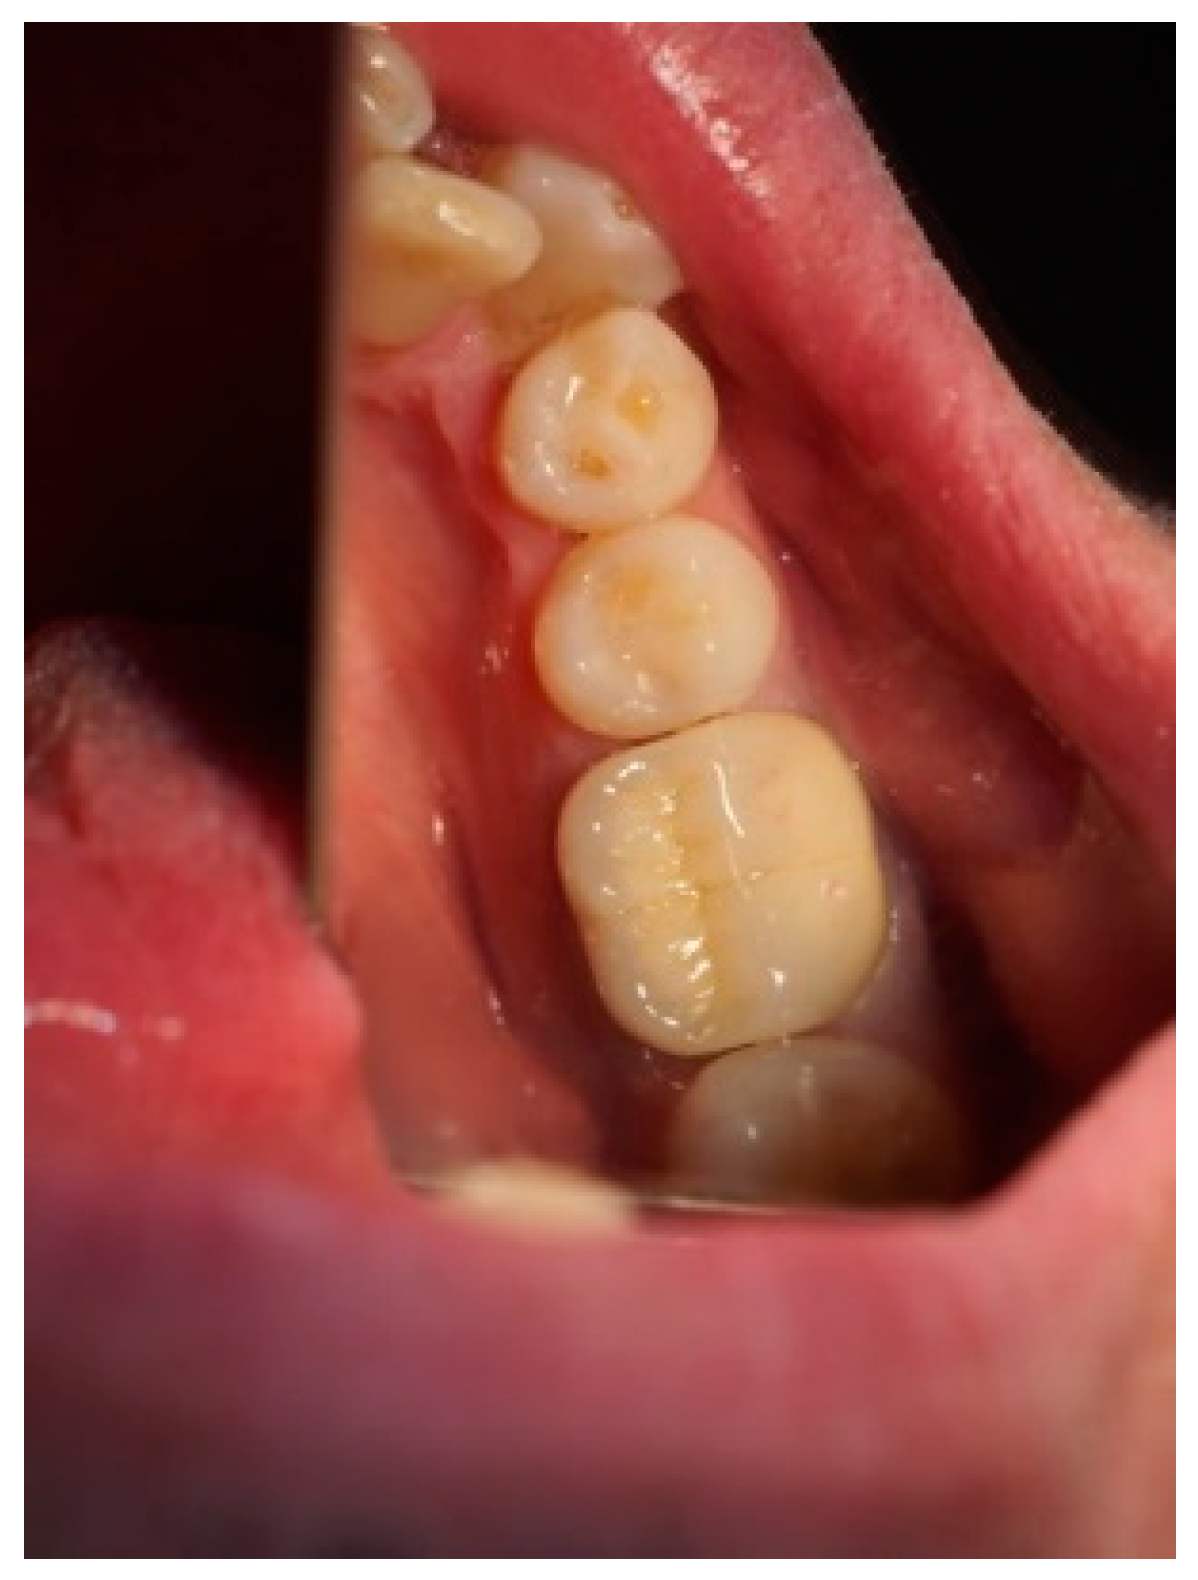

Figure 3, Figure 4, Figure 5, Figure 6, Figure 7 and Figure 8 display the follow-up of the healing process after a resective procedure for lengthening a short clinical crown with a laser.

Figure 8.

The cemented permanent metal–ceramic crown.